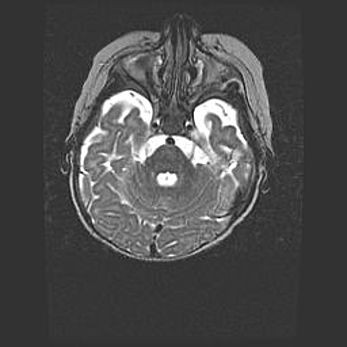

Мальформация Денди-Уокера. Киста задней черепной ямки.

Агенезия мозолистого тела.

Возраст: 2,5 месяца

Вес: 2420 г

Пол: женский

Окружность головы: 37 см

Срок гестации: 32 недели

Мальформация Денди—Уокера — редкий вид патологии ЦНС, представляющий собой врожденный порок развития каудального отдела ствола и червя мозжечка, ведущий к неполному раскрытию срединной (Мажанди) и латеральных (Лушка) апертур IV желудочка мозга. Для этогно синдрома характерна триада симптомов: гипотрофия червя мозжечка и/или полушарий мозжечка, кисты задней черепной ямки, гидроцефалия различной степени. В 70% случаев порок сочетается и с другими аномалиями головного мозга, в частности с агенезией мозолистого тела.